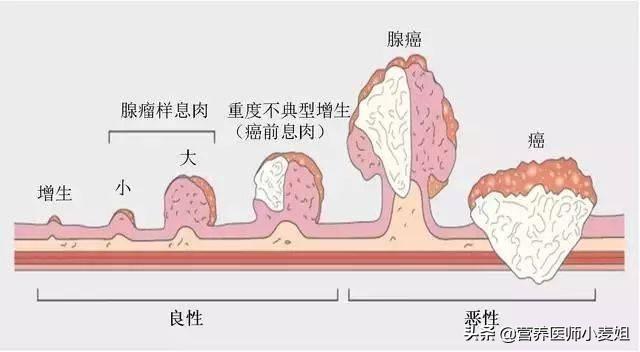

腸ポリープはがん化する可能性もあり、ポリープが複数ある場合は、早期の大腸がんを避けるため、定期的なフォローアップの大腸内視鏡検査と定期的な生検を受けるよう促す必要があるかもしれない。

腸の腺腫様ポリープ → 腸がん

腸ポリープは、腺腫性ポリープ、炎症性ポリープ、過形成性ポリープに分類される。腺腫性ポリープは5~15年でがんになる可能性がある。炎症性ポリープと過形成性ポリープは、現在のところ癌化する可能性は低いと考えられているが、大腸内視鏡下ではポリープの性状を形態学的に判断することができないため、一般的には大腸内視鏡下で切除し、病理標本にすることが推奨されている。最終的な判定が腺腫性ポリープであったとしても、また嵐の中で "リーキーフィッシュ "を起こさないように、毎年検査を受ける必要がある。

ポリープは間違いなく癌の弟分だが、非常に簡単に癌になる可能性がある。

腸ポリープ

最も有望なミニオンは以下の通り。結腸・直腸ポリープ癌にエスカレートする可能性が最も高く、多くの場合、複数の分布があり、通常は隠れた増殖で、「変形」が結腸癌になることもある。

腸ポリープには大きく分けて炎症性と腺腫性の2種類があり、前者はほとんどが悪性ではなく、後者は悪性の可能性が高い。

統計上、大腸がんの80~95%は腸ポリープから段階的に進行し、その過程には5~10年かかる!

ポリープから癌への進行性進展

5.腸管ポリープ:家族性多発性腸管ポリープ症は染色体優性疾患であり、一つの遺伝子が多面的に発現する。大腸ポリープは腺腫性ポリープであり、発癌率は50%である。病気の経過の延長、加齢、免疫力の低下により発癌率はさらに高くなり、家族歴があれば男女ともに罹患する可能性がある。家族歴があると男女ともに大腸腺腫性ポリープが発生し、次の世代の年齢が進み、20歳前に大腸腺腫性ポリープがんが発生することさえある。また、一般的な腸管ポリープでも発癌のリスクはあり、腸管腫瘍の大部分は腸管腺腫から緩徐に発生する。 ポリープが大きいほど発癌率は高く、ポリープの数が多いほど発癌率は高く、ポリープの病理学的タイプでは腺腫性絨毛成分が多いほど発癌率は高く、先端部のある腺腫性ポリープは発癌率が低く、基部の広い腺腫性ポリープは発癌率が高く、直腸ポリープは発癌率が高い。

- 腸癌の前癌病変としての大腸多発性腺腫性ポリープ.大腸で増殖するため発見が容易ではなく、血便、粘液便、腸重積を呈することがあり、主に大腸内視鏡検査で発見される。定期的なフォローアップ大腸内視鏡検査で腸癌への進行を防ぐ。